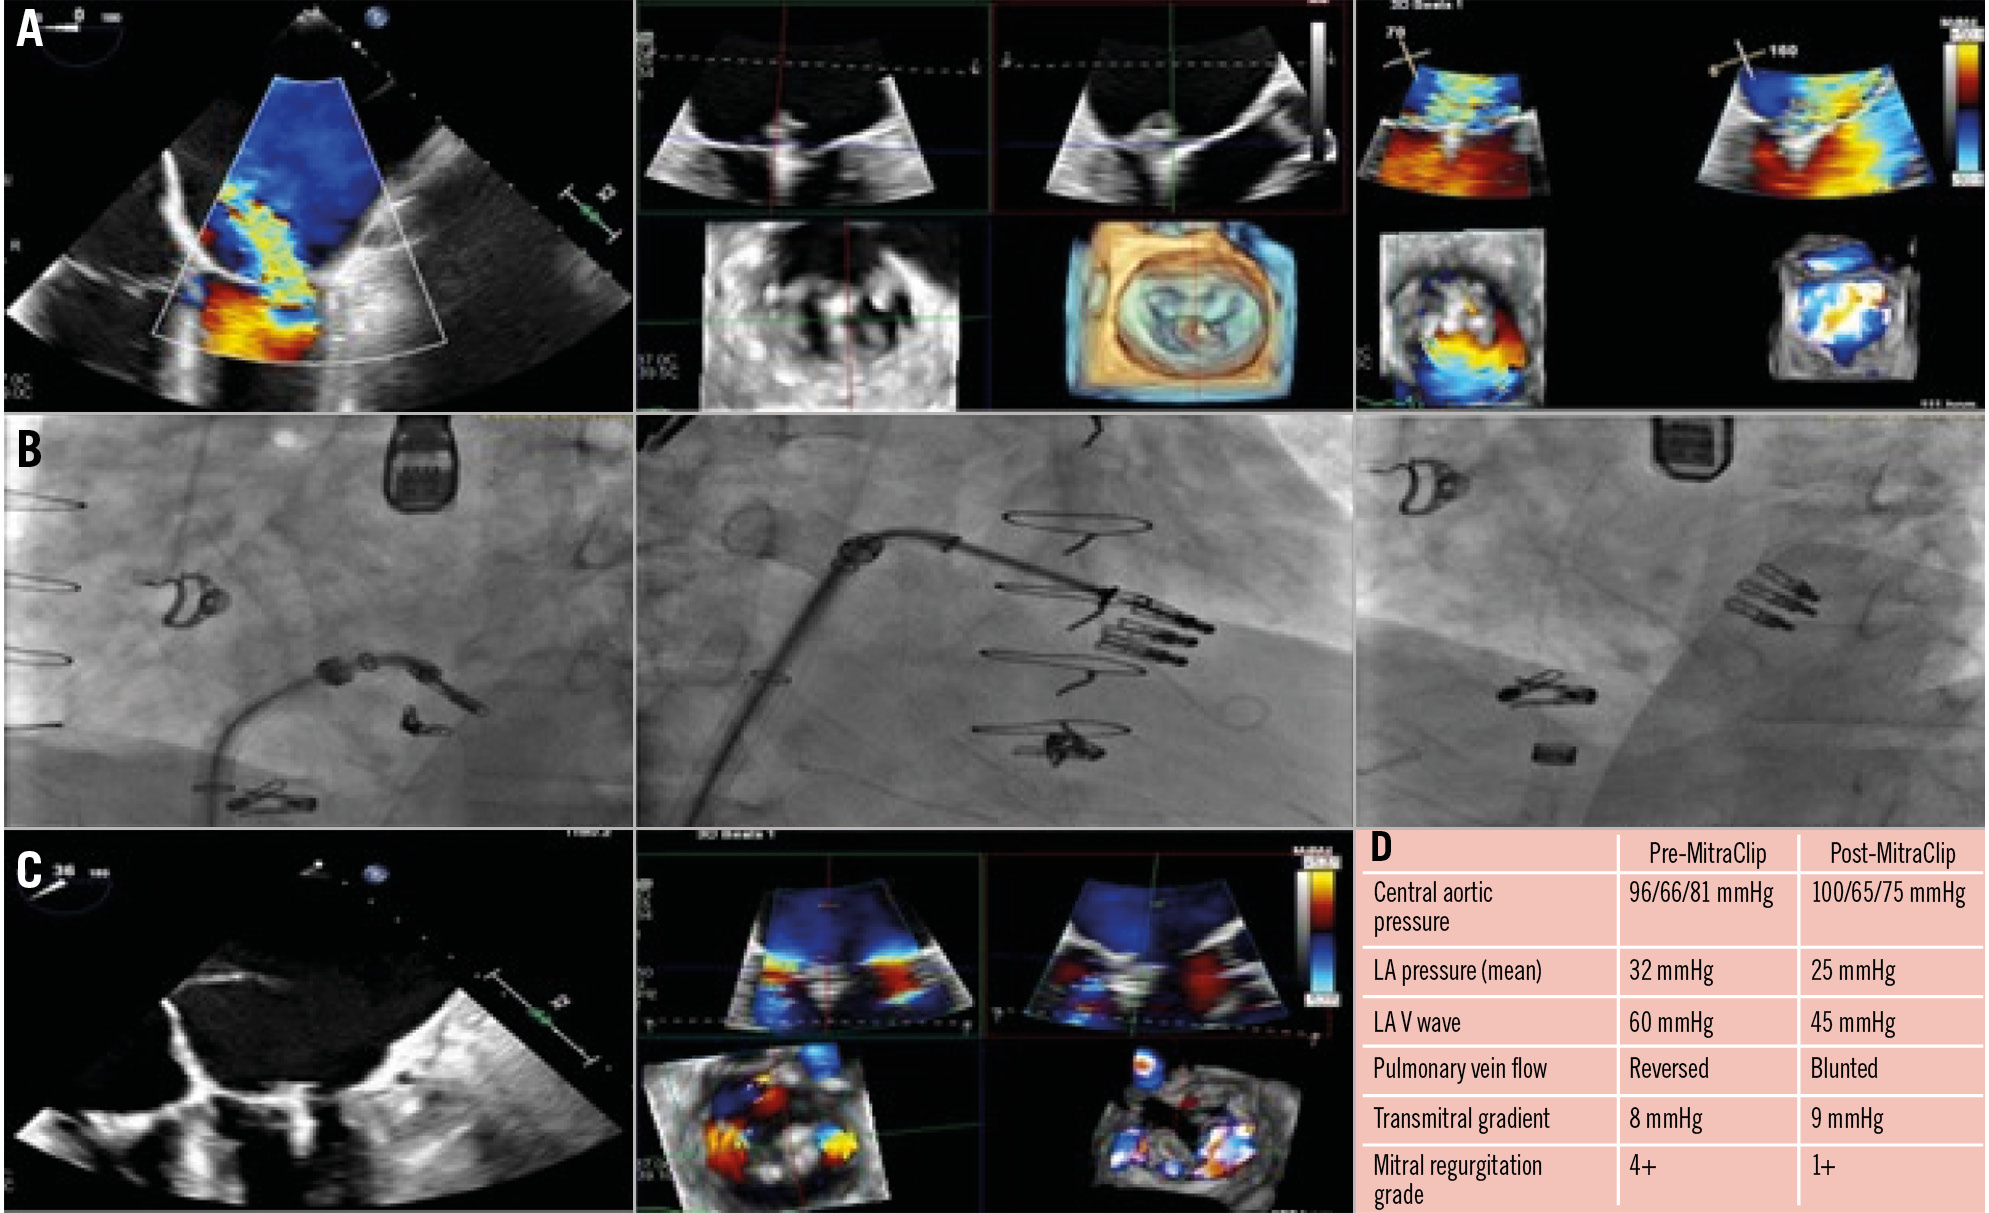

Single leaflet device attachment (SLDA) is defined as the loss of a single device leaflet during insertion against the opposing leaflet. SLDA was seen in 2.2% of patients in the EVEREST highârisk registries86, 4.8% of patients in the ACCESS-EU registry89, and 1.5% in the TVT registry87. Risk factors for SLDA include flail leaflet, a large effective regurgitant orifice area (EROA), and a small mitral valve (MV) orifice area86. Options for managing SLDA include placement of an additional clip, surgical MV repair or medical management. Data from the ACCESS-EU registry90 showed that of the 27 patients who had SLDA (out of 567 included patients), 10 underwent a second MitraClip procedure, 6 underwent surgical MV repair or replacement, and 11 were treated medically. Most clips detach acutely (during the procedure) or subacutely (first days after the procedure), while late SLDA is infrequent. Meticulous TOE assessment during leaflet grasping and device deployment helps prevent SLDA. In our practice, contemporary TOE imaging using live 3D multiplanar reconstruction is the default modality and has proven invaluable in both preprocedural diagnostic imaging and procedural guidance (Figure 8, Supplementary Figure 1). In addition to the live images, acquisition of full 3D volumes allows the imaging specialist to pause, reanalyse and reconstruct the grasping phases in an almost infinite number of planes to provide either reassurance of clip stability before release or demonstrate the need for regrasping. Appropriate leaflet grasping should be confirmed in multiple TOE views, including the longâaxis view prior to device deployment. Kreidel et al90 reported their experience from Germany of 21 patients undergoing a second MitraClip procedure for recurrent MR. They observed an 85% success rate of repeated MitraClip in patients without loss of leaflet insertion (LLI) versus only 25% success in those with LLI. In a multicentre registry91, a total of 147 cases of MitraClip failure were noted; these were secondary to LLI in 31.9% of cases, SLDA in 67.3% of cases, and clip embolisation in 1 case. In all, 48% had conservative management, followed by MitraClip in 35%, and surgery in 17%. Survival analysis suggested a trend towards a better outcome for those patients with redo MitraClip, and multivariable analysis demonstrated a survival benefit for redo MitraClip.

Figure 8. Treatment of a 52-year-old male with a history of dilated cardiomyopathy s/p heart transplant, MR and TR s/p mitral and tricuspid TEER (1 MitraClip XT [Abbott] on the MV, 2 XTs on the TV), and CKD, with recurrent severe MR in the setting of single leaflet detachment. A) TOE images showing severe MR (4+) with anterior translocation of the posterior clip with attachment to posterior leaflet tips (SLDA) along with moderate-severe TR (3+) originating adjacent to the clips. B) Fluoroscopy images. First, the MitraClip XT was placed medial to the prior clip, and then a second MitraClip XT was placed lateral to the prior clip. C) TOE images with a reduction in MR grade from 4+ to 1+ following redo MitraClip. There was a significant improvement in haemodynamics, as shown (D). CKD: chronic kidney disease; LA: left atrial; MR: mitral regurgitation; MV: mitral valve; SLDA: single leaflet device attachment; s/p: status/post; TEER: transcatheter edge-to-edge repair; TOE: transoesophageal echocardiogram; TR: tricuspid regurgitation; TV: tricuspid valve